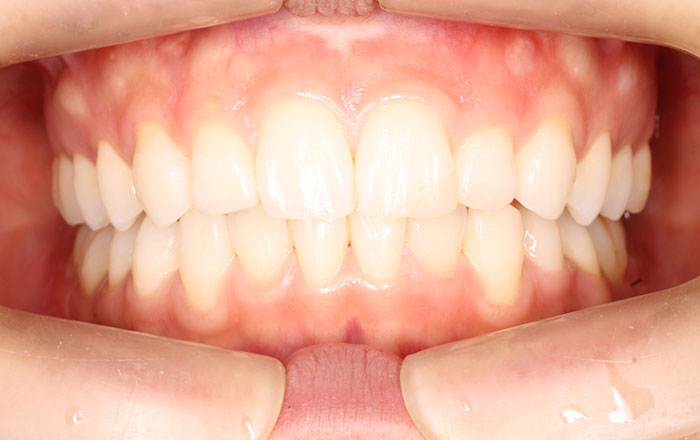

①矯正で理想の噛み合わせに近づける

歯列矯正を行って、理想の噛み合わせに近づけることで、歯や顎の不快さなどの軽減が期待できます。

噛み合わせが良くない状態で強く噛んでしまう部位がある場合は、歯全体で噛めるように治療していきます。

※矯正は、歯ぎしり・食いしばりを完全になくすものではありません。